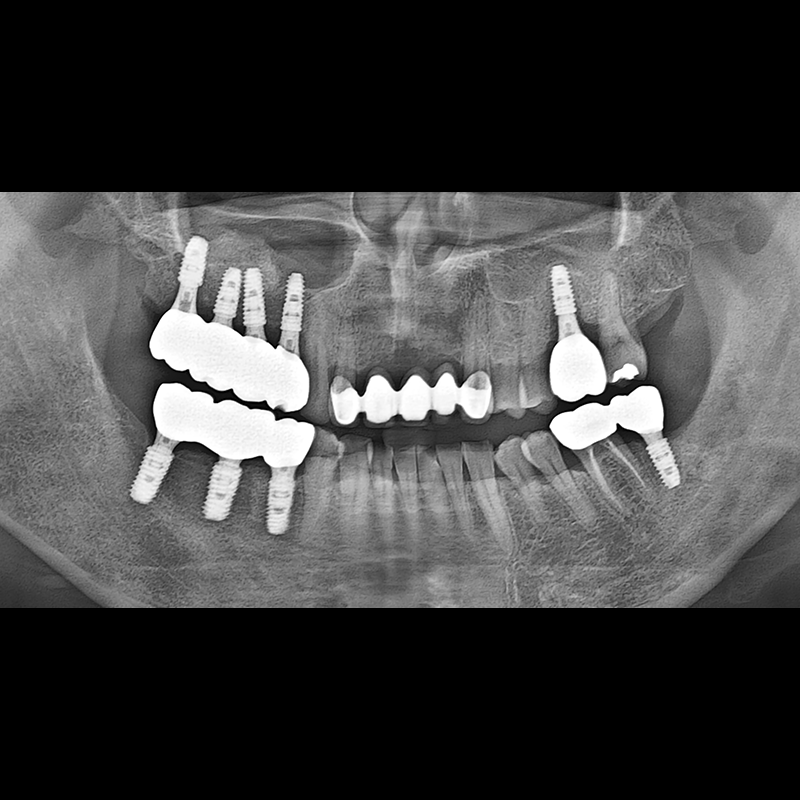

BEFORE AFTER

种植牙前后的照片 2025.05.30

在缺失的牙齿部分和难以挽救的牙齿位置植入了种植牙。